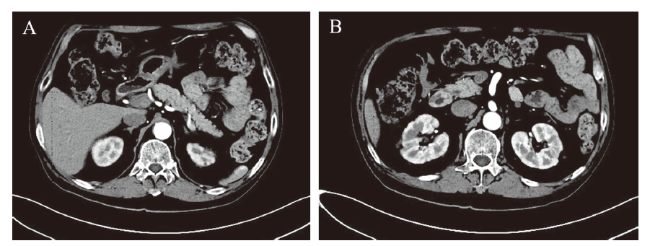

血淀粉酶明显升高,波动于556~1106 U/L ,血脂肪酶(参考值13~60 U/L)和尿淀粉酶(参考值0~1200 U/L)则始终在正常范围。见图1。血清肌酐和尿肌酐亦在正常范围。见表1。腹部彩色多普勒超声(彩超)示胰脏未见明显异常。腹部CT示肝、胆、胰、脾未见异常,胰腺显影良好,大小形态正常,实质平扫及CT增强扫描未见明显异常信号影。见图2

图2 大疱性类天疱疮并巨淀粉酶血症患者腹部CT图